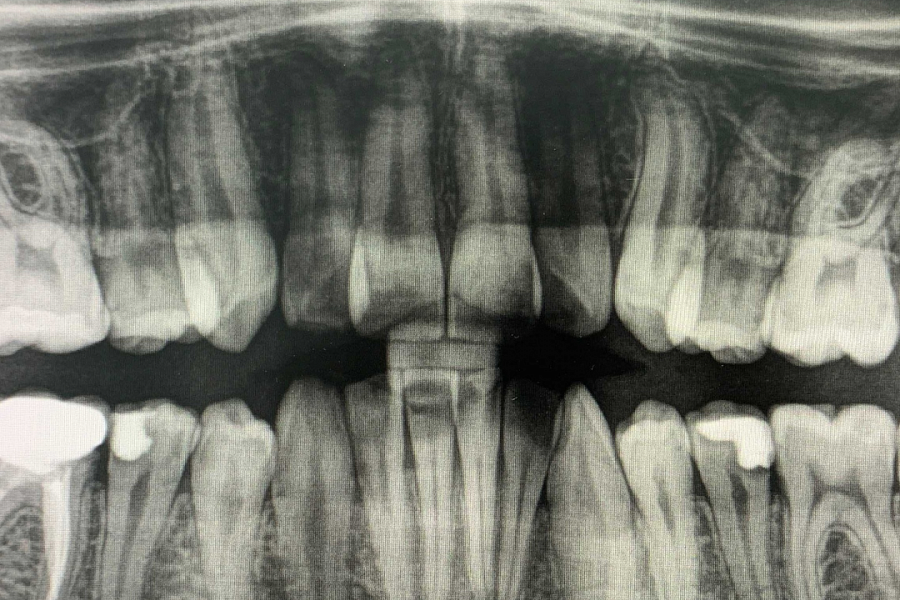

Пациент направлен стоматологом-терапевтом с целью удаления восьмерки зуба мудрости слева внизу из-за невозможности пролечить кариес между восьмым и седьмым зубом.

Восьмерка имеет наклон в горизонтальном направлении и упирается в седьмой зуб. Сложность в том, что зуб находится на нерве, и ошибки при удалении таких зубов могут привести в последствии к онемению губы и подбородка со стороны удаляемого зуба.Этапы лечения

Зуб был фрагментирован на несколько частей и удалён. После были наложены швы. Онемение не наступило.